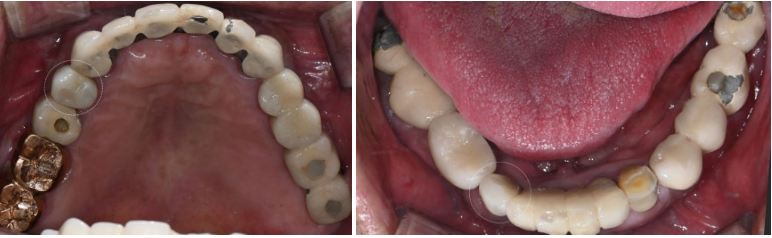

골유착이 완료되면 임시 치아를 통해

연조직의 형태를 조정하고

환자의 기능적, 심미적 요구사항을 확인합니다.

2025.6.8

임시 치아 기간을 통해 적절한 치은 형태가 형성되면,

최종 보철물을 제작하게 됩니다.

2025.6.16

현재 가장 널리 사용되는 지르코니아 보철물은

뛰어난 강도와 생체 적합성,

그리고 자연치와 유사한 심미성을 제공합니다.